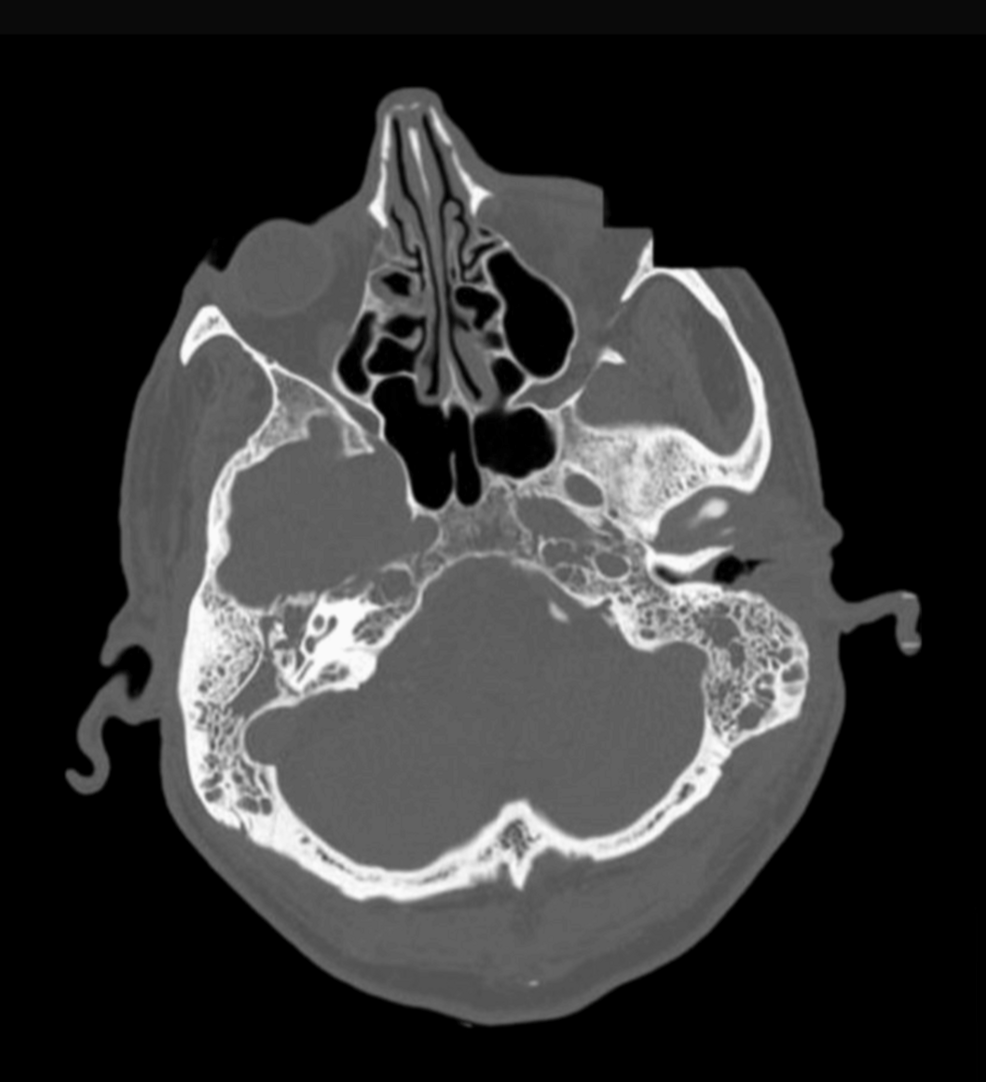

Predictive diagnostic models for newly diagnosed diabetes mellitus in moderate to severe COVID-19: the role of TyG Index, BMI, and inflammatory markers | BMC Endocrine Disorders

In this cross-sectional pilot study of patients hospitalised with moderate to severe COVID-19, over half developed newly diagnosed DM after excluding those with pre-existing DM. Our findings support the hypothesis that IR, rather than insulin…